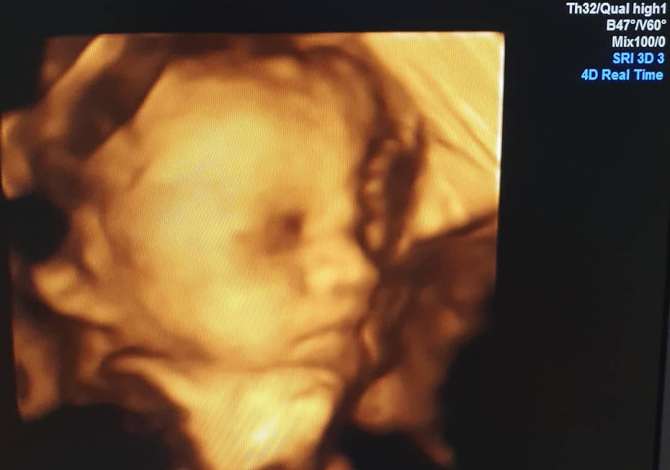

🩺 Klinika Gjinekologjike Dr. Kozeta

Ā Obstetrike-Gjinekologji

āž”ļø Procedurat:Ā Egzaminimet gjinekologjike, ekografi gjinekologjike dhe obstetrikale, kolposkopi, planifikim familjar, nderhyrje gjinekologjike